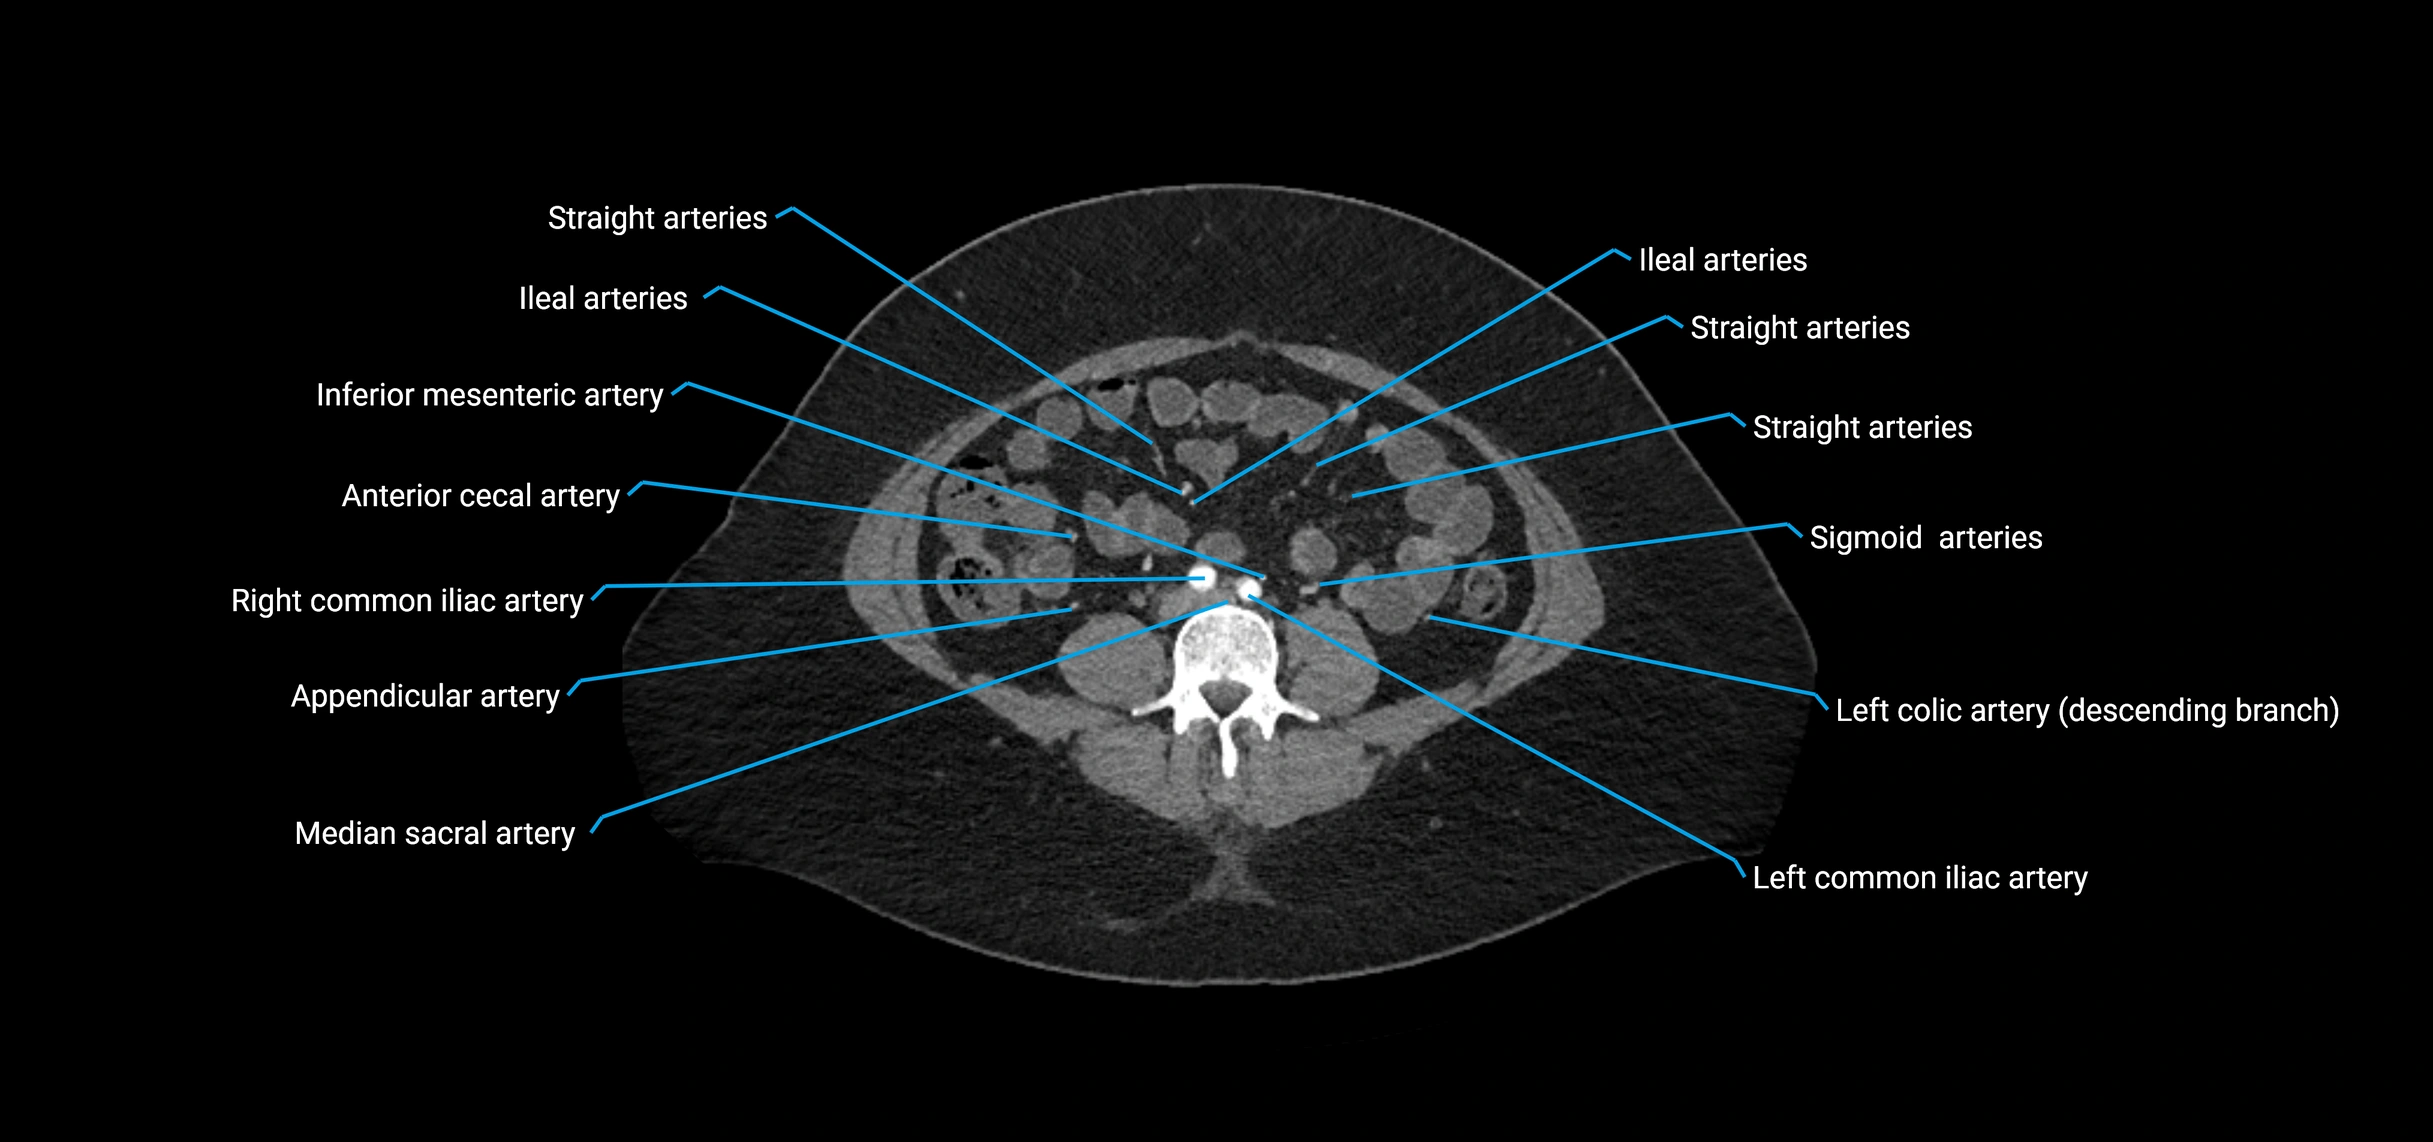

Contrast-enhanced CT (CTA):

• Gold standard for abdominal aortic imaging

• Provides excellent detail of lumen, wall, aneurysm, thrombus, and branch vessels

• Multiplanar and 3D reconstructions help in aneurysm measurement, stent graft planning, and dissection evaluation

• Detects acute rupture, traumatic injury, or occlusion with high sensitivity